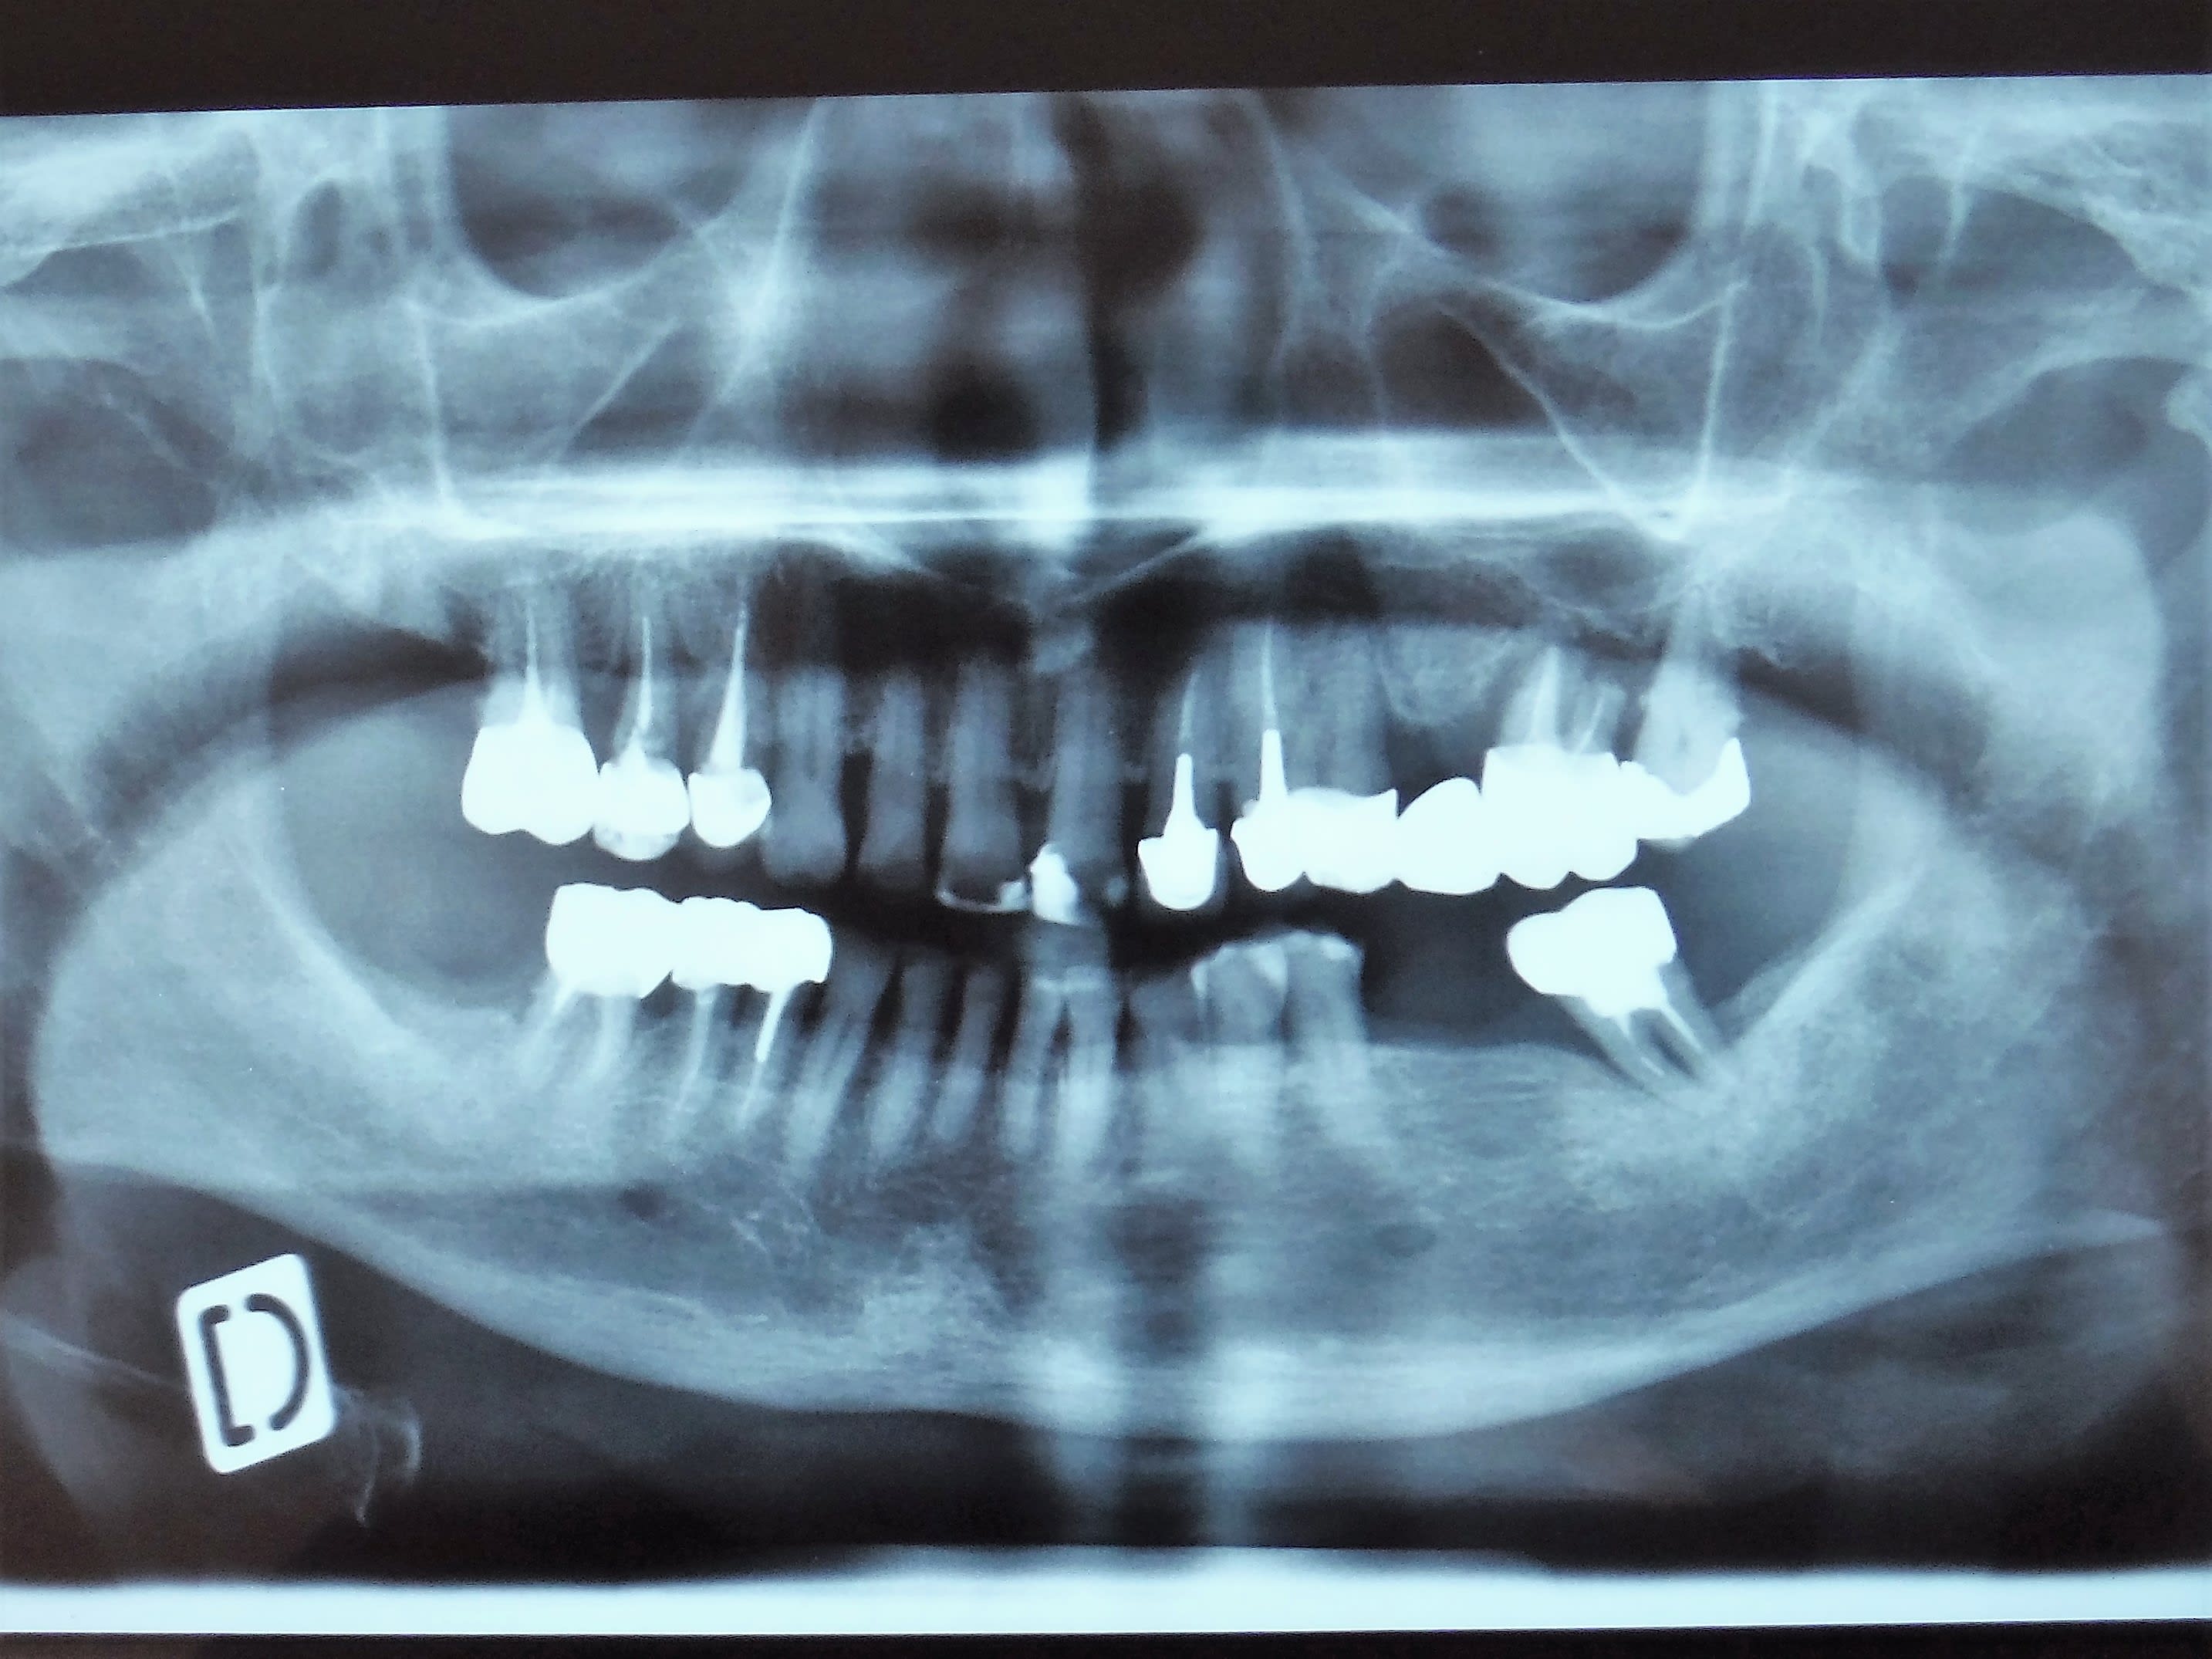

Alors j'ai viré 24, 26 pour 27 on attendrait un peu. Et en secteur 1 la 15, rapport aux images osseuses, et puis c'est toujours bien (mieux) d'avoir 2 édentements encastrés, un de chaque coté, mieux pour les crochets et une dent proth de droite et de gauche cela équilibre bien (putain j'avais un prof macroniste! avec 30 ans d'avance)

La patiente à une patho inflammatoire chronique qui se traite à la cortisone... ostéoporose (médicamenteuse?)... biphosphonates à gogo, les implants on oublie. Déjà pour les exos je serre les fesses.

Le truc c'est qu'elle ne pouvait toujours pas manger, douleur à la pression secteur 1.

"ça me fait mal à la molaire, je peux pas manger de ce coté"

J'ai pensé à un MV2 sur la 16... allez va pour exo de la 16, sous AB protocole... je l'avais pris entre deux, j'ai pas trop regardé j'avoue... elle dit molaire, c'est molaire.

Revenons à ma patiente, toujours douleur à la pression. "C'est la molaire Docteur" (j'aime bien quand on m’appelle Docteur, au moins le patient est conscient d'où il est et avec qui, "Monsieur", j'ai un doute... ).

Jour de l'exo, Ab Ok (tjrs vérifier chez les vrais malades), et là, il faut en convenir ma patiente ne parle pas la même langue que moi. Oui parce que la molaire... bin c'est la 14, mobilité axiale, sondage positif en dv pour recherche de fracture.

Exo et zolie fêlure de l'apex à la couronne prothétique, c'était bien la peine de ne pas avoir mis d'IC ou de tenon afin de prévenir ce risque :-)))

Je me demande même si un bête screw-post n'aurait pas évité le problème?-(

Je l'ai autopsié, il n'y avait que du composite, de la gutta et du ciment dans la racine.